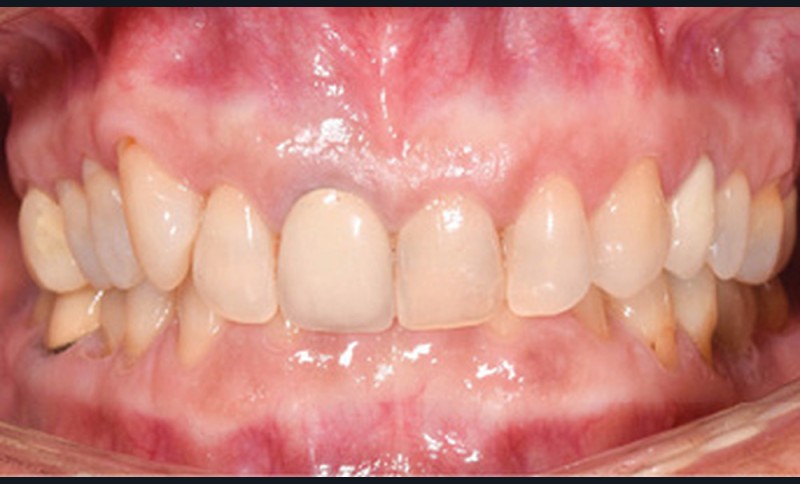

Examen endobuccal (fig. 2a-e)

L’arcade maxillaire est asymétrique et parabolique. Elle présente une mésio-position du secteur 1. On note des rotations mésio-vestibulaire de 13 et disto-vestibulaire de 23 et une palato-version incisive. Les restaurations prothétiques sur 11, 16 et 24 semblent à refaire. L’arcade mandibulaire est asymétrique et parabolique avec une couronne sur implant en 36.

Dans la dimension transversale, on constate une endoalvéolie maxillaire. Dans la dimension sagittale, on observe une classe II plus importante à droite où elle est complète de 5 mm. Le surplomb est absent et la supraclusion totale (6 mm) par supra-alvéolie mandibulaire.